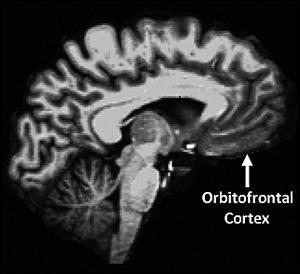

La corteza orbitofrontal,

que forma parte de la región prefrontal

y está implicada en los procesamientos

socio/emocionales,

mostró asociaciones similares

con la personaldiad.

Fuente: Universidad de Washington.

La corteza orbitofrontal, que forma parte de la región prefrontal y está implicada en los procesamientos socio/emocionales, mostró asociaciones similares con la personalidad. Antes de ser sometidos al escáner, los participantes aportaron asimismo datos sobre su personalidad.

La combinación de información permitió establecer que los individuos más neuróticos presentaban volúmenes más pequeños de materia gris en las áreas temporal media y frontal del cerebro que los individuos menos neuróticos. Un patrón opuesto fue constatado en el caso de la escrupulosidad.